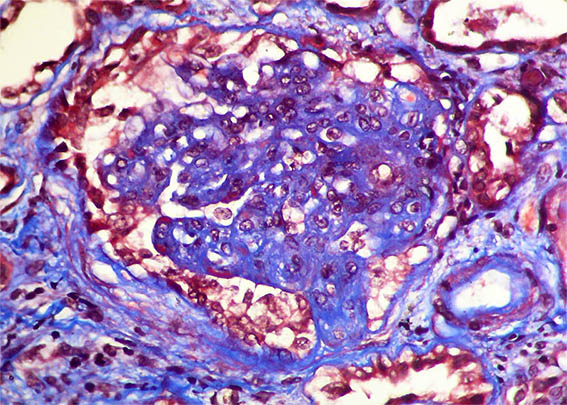

Figura 4. Tricrómico de Masson, X400. Lesión esclerosante segmentaria y posible pequeña semiluna epitelial en la parte inferior.